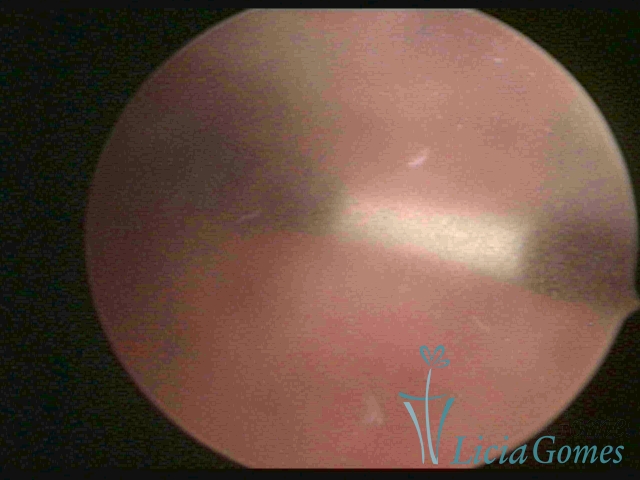

Canal cervical trófico, com o fio de Mirena®